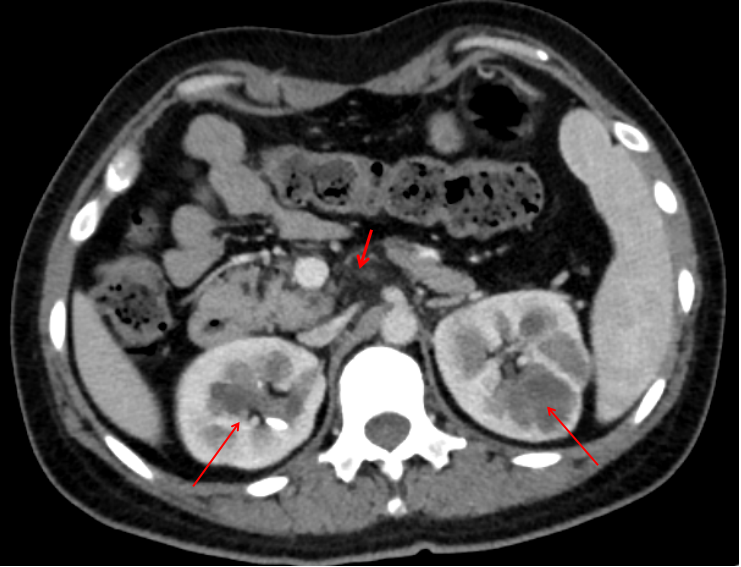

进一步查腹部增强CT示胰腺体尾部缺如;两肾多发囊肿及复杂囊肿(图1)。完善肝穿刺示肝细胞内明显胆汁淤积伴胆管缺失(图2)。结合患者病例特点:青年女性,有糖尿病、抑郁症病史,肝功能示GGT正常的胆汁淤积(TB、TBA、AKP升高)、影像学排除梗阻,查见胰腺体尾部缺如;两肾多发囊肿及复杂囊肿。检索相关文献,可能符合糖尿病肾囊肿综合征表现,该病是以“糖尿病、胰腺缺失、双肾囊肿”为主要表现的遗传代谢性疾病,可有神经精神异常,肝功能表现为胆汁淤积。遂进一步完善基因测序:测出HNF1β拷贝数缺失(17q12微缺失),系致病性变异(图3)。患者最终诊断为“肾囊肿和糖尿病综合征、胆汁淤积性肝炎、抑郁症”。分析患者此次发病,可能在肾囊肿和糖尿病综合征基础上,妊娠及药物使用诱发胆汁淤积加重。

图1